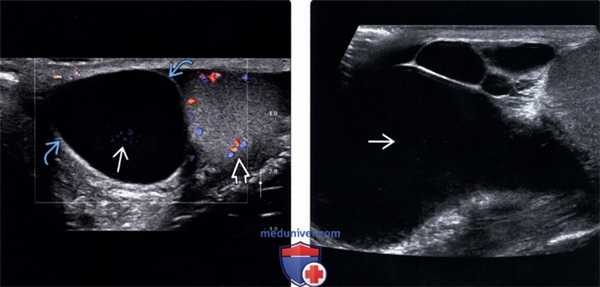

(Слева) Крупное сперматоцеле кверху от правого яичка, содержащее точечный низкоинтенсивный эхосигнал с артефактами на соответствующей допплерографии. В режиме реального времени эти точечные очаги были подвижны.

(Справа) УЗИ в продольной плоскости, В-режим: визуализируется сложное кистозное образование с многочисленными камерами с наличием взвеси, что является характерными признаками сперматоцеле.